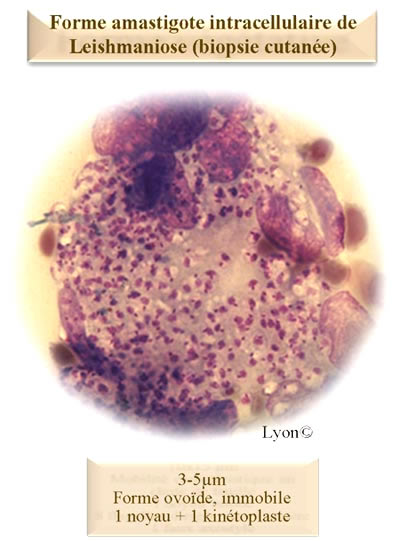

Leishmania sp.

forme amastigote leishamieMemoBio©